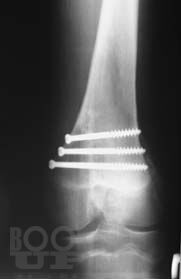

Книга посвящена сложному и разнообразному разделу травматологии – диагностике травматических повреждений крупных суставов у взрослых и детей. Приведены основные рентгеноанатомические сведения о суставах. Дана рентгенологическая характеристика разнообразных повреждений костей и мягких тканей, доступных рентгеновскому исследованию. Представлена рентгенологическая картина посттравматических, в том числе послеоперационных воспалительных осложнений – артритов.